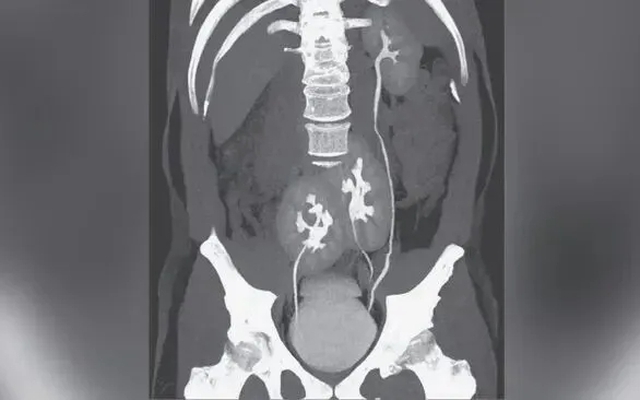

Đi khám nhiễm trùng tiết niệu, người đàn ông 31 tuổi phát hiện có 3 quả thận

Sống khỏe 2026-04-07T17:15:00Bệnh nhân thậm chí không bao giờ nhận ra mình có thêm một quả thận trong suốt cuộc đời.